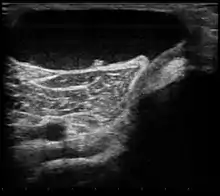

| Ultrasound image of Baker's cyst | |

Diagnosis is by examination. A Baker's cyst is easier to see from behind with the patient standing with knees fully extended. It is most easily palpated (felt) with the knee partially flexed. Diagnosis is confirmed by ultrasonography, although if needed and there is no suspicion of a popliteal artery aneurysm then aspiration of synovial fluid from the cyst may be undertaken with care. An MRI image can reveal presence of a Baker's cyst.